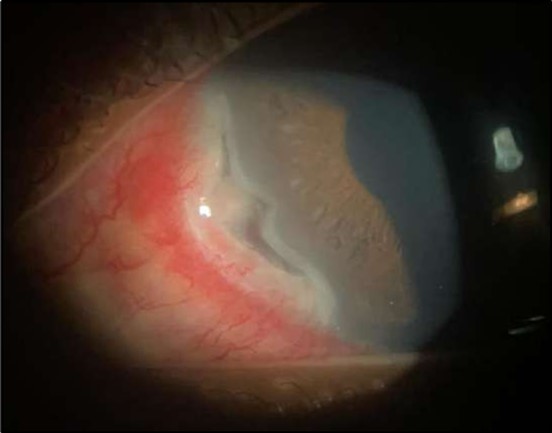

On the current presentation, Snellen VA was 6/6 in the right eye and 6/9 in the left eye, with normal IOP. The left eye demonstrated mild upper lid edema and intense nasal ciliary injection. Slit-lamp evaluation revealed a crescentic area of stromal corneal melting between 7 and 10 o’clock nasally, with overhanging edges and a fluorescein-positive base. No corneal infiltrates were present, and the surrounding stroma remained clear. The anterior chamber was deep and quiet, lens was transparent, pupil was round and reactive & normal posterior segment. Anterior segment optical coherence tomography (AS-OCT) confirmed a localized ulcer, measuring 1324 µm in horizontal width and extending to a depth of 380 μm, compared with an adjacent healthy corneal thickness of 824 µm, corresponding to approximately 46.1% stromal thinning (Figure 1a, Figure 1b, Figure 1c)

Figure 1a.Left eye (OS), on presentation. Slit-lamp image: crescent-shaped peripheral corneal ulceration located nasally, with severe adjacent conjunctival injection, peripheral thinning, and stromal infiltration.

Figure 1b.OS, Fluorescein-stained slit-lamp image: positive uptake at site of epithelial defect.

Figure 1c.Right eye (OD), Slit-lamp photo with a faint peripheral, inferonasal, small non-significant scar vascularization.